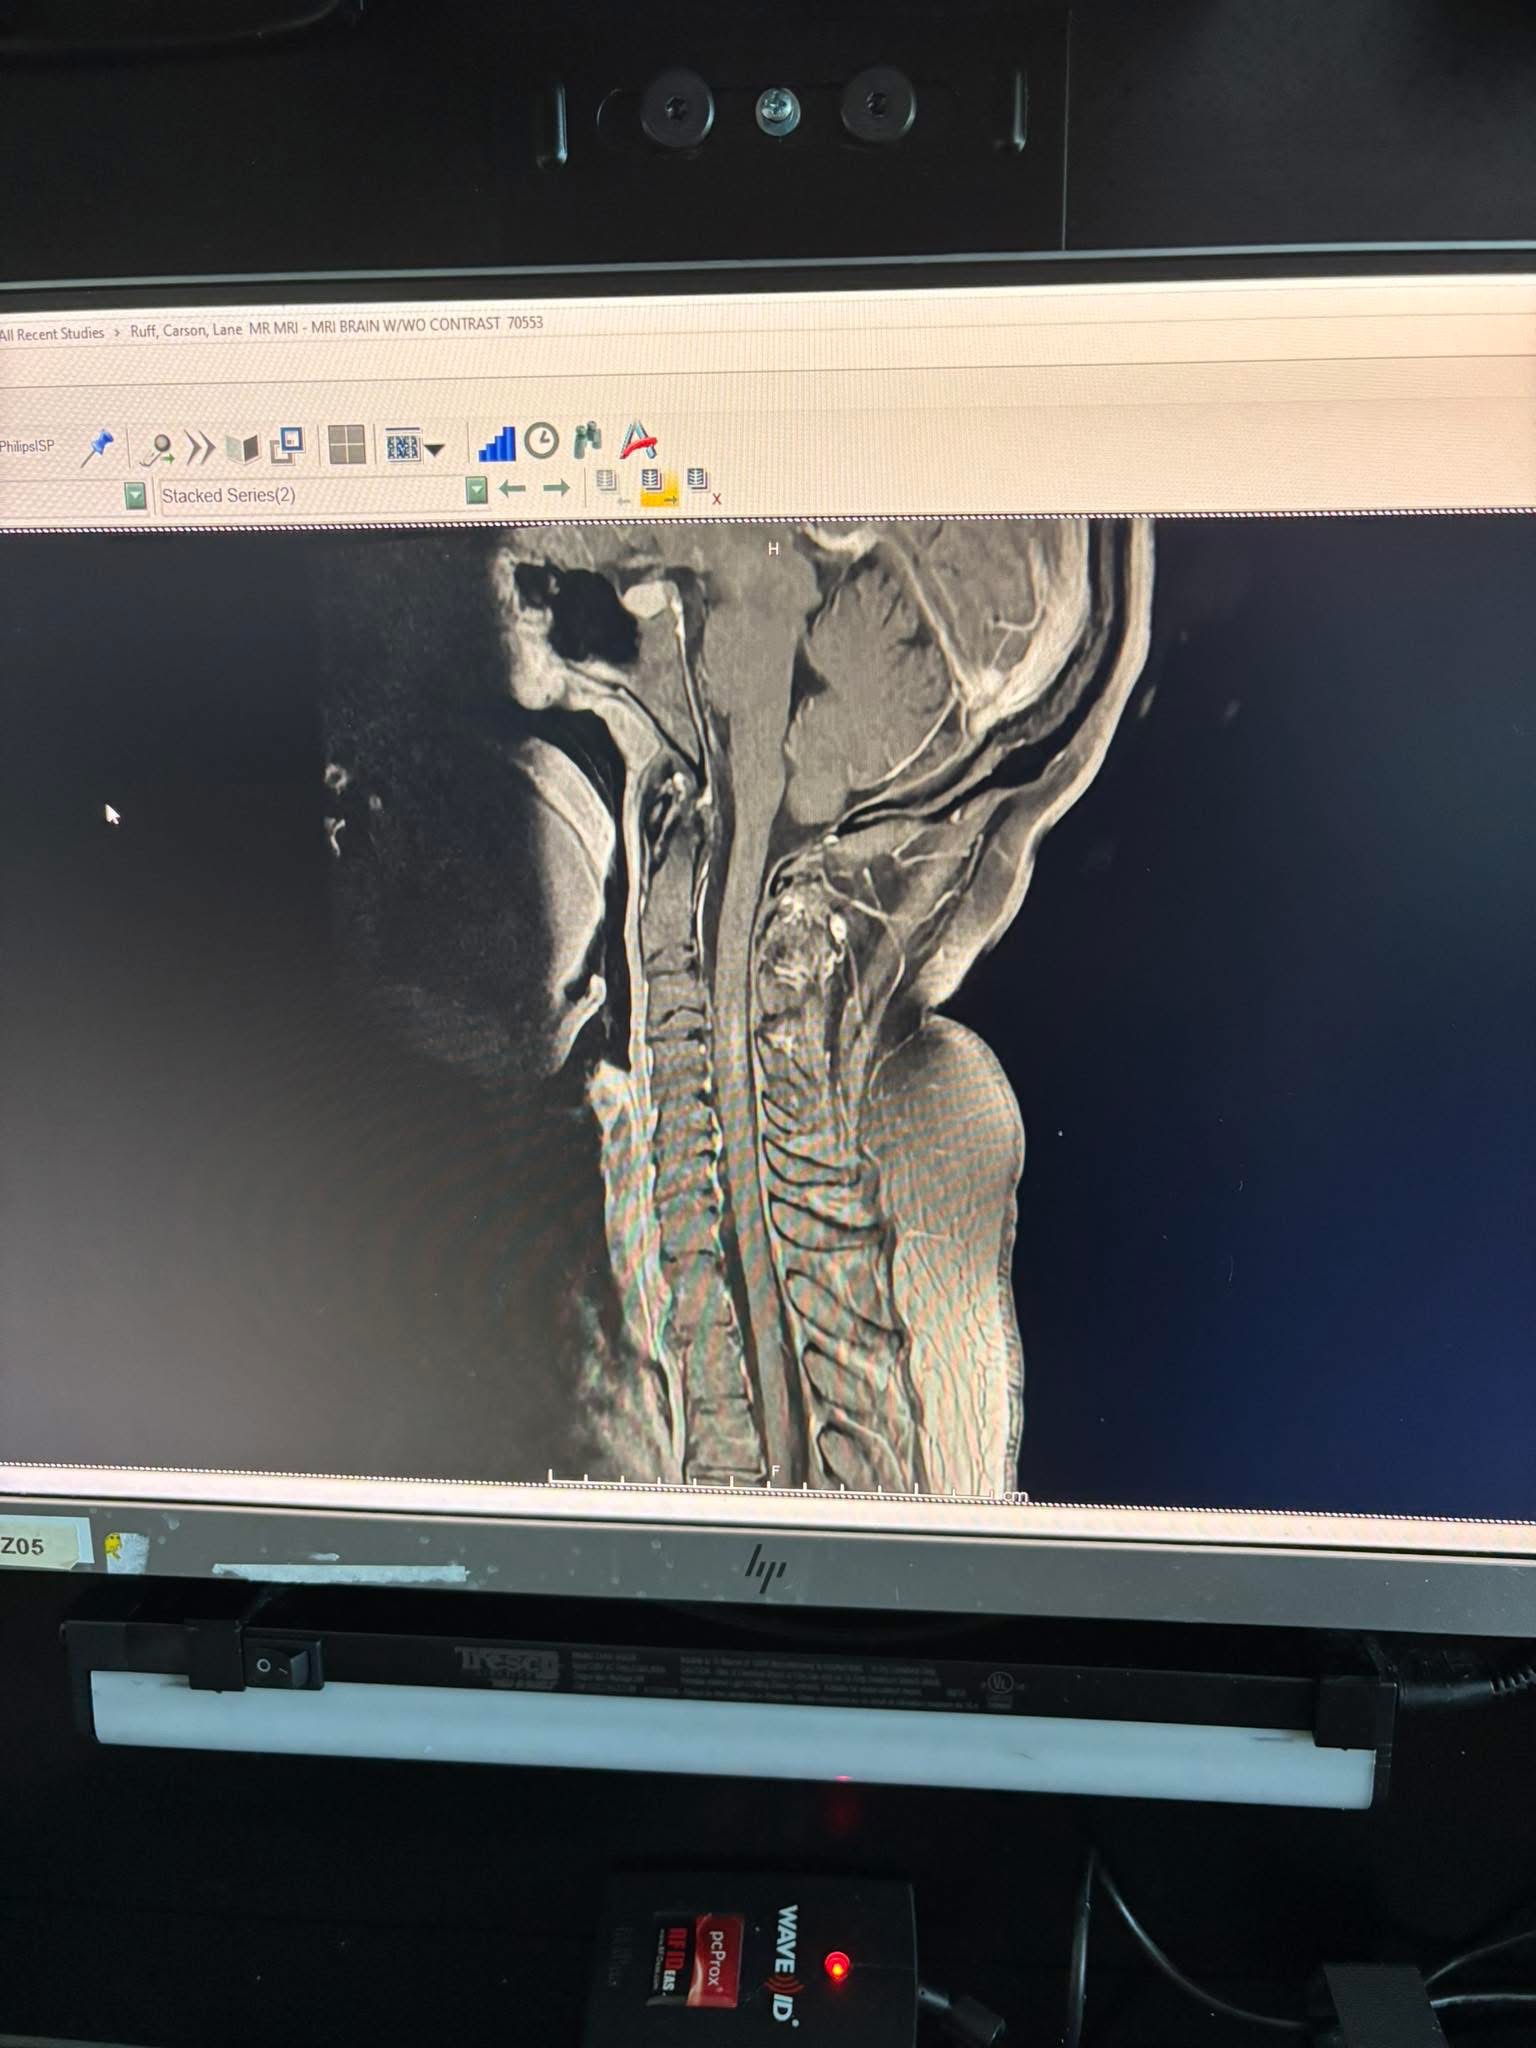

I’m raising funds because my friend Carson Lane Ruff recently got diagnosed with a form of multiple sclerosis. She is such a kind soul, worship singer leader, disciple of Jesus and a mother to a young boy. We’re just asking that you be kind enough, to give her a few dollars to help her as her body recovers from paralysis so she can take care of her family and keep her house. She is a home care nurse so , she has no way to work until her body is fully recovered. If you can’t donate please lift up the Ruff family in prayer!